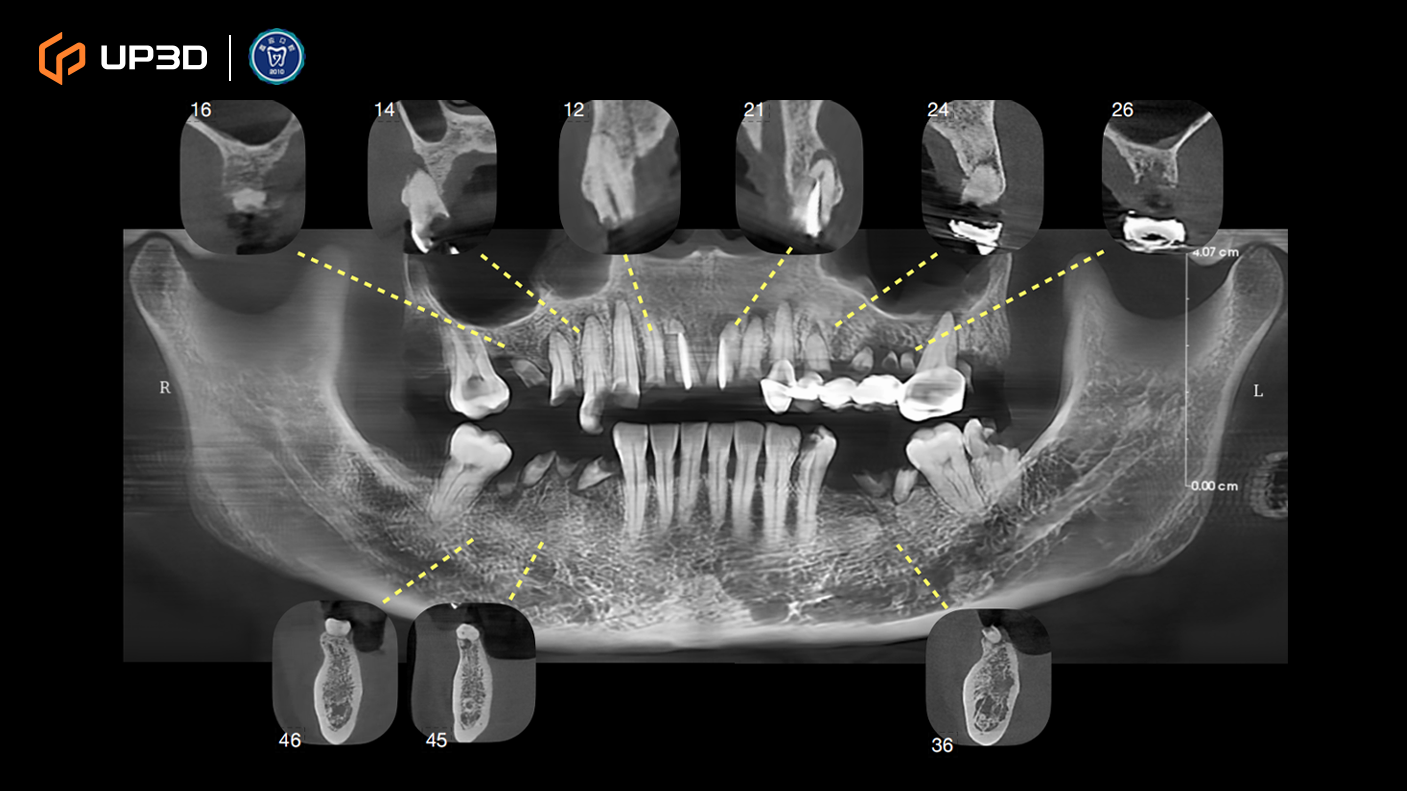

2.3 Radiographic Assessment

A panoramic radiograph and cone-beam computed tomography (CBCT) revealed multiple missing teeth and uneven alveolar ridge resorption, with moderate-to-limited bone volume in selected areas. Based on measurement and analysis, implant placement was planned at sites including 16, 14, 12, 21, 24, 26, 36, 45, and 46 (FDI tooth numbering).

Intraoral scan data were merged with CBCT to complete a 3D implant plan:

Six implants planned in the maxilla and three implants in the mandible

Surgical guide (guided surgery) pathways were planned digitally

Digital tooth setup and guide fabrication supported accurate positioning and a minimally invasive approach

Guided surgery helped improve consistency in implant angulation and depth control, supporting a stable foundation for immediate loading.